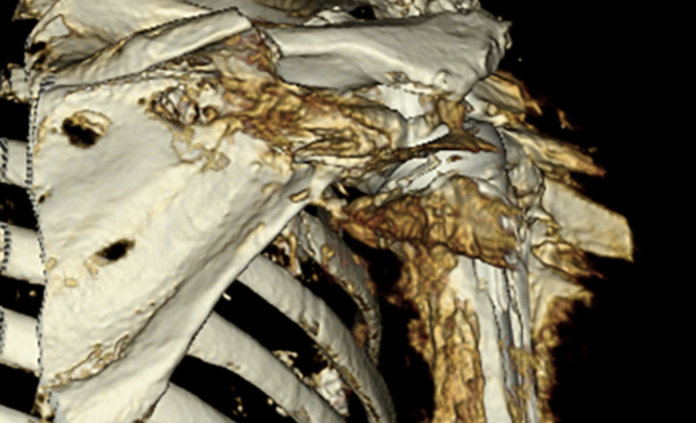

(1) Acromial and scapular spine stress fractures are clinically important complications of reverse total shoulder arthroplasty (RSA), occuring in 3-11% of cases and often resulting in poor functional outcomes such as persistent pain and limited active motion.

Fractures